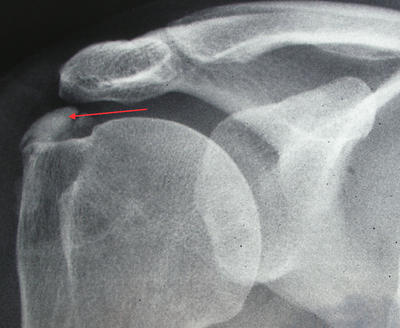

Kalcificirajući tendinitis ili kalcificirajuća tendinopatija (vapno u ramenu) čest je poremećaj nepoznate etiologije koji se očituje nakupljanjem depozita kalcija u tetivama rotatorne manšete uz spontanu resorpciju kalcifikata i posljedično cijeljenje tetiva. Za vrijeme odlaganja kalcija bolesnik je uglavnom bez većih tegoba. No, za vrijeme resorpcije kalcifikata rame je izrazito bolno zbog nastale vaskularne proliferacije te porasta intratetivnog tlaka. Za vrijeme formativne faze bolesnik se žali više na nelagodu nego na bol. Naprotiv, u akutnoj, resorptivnoj fazi bol je toliko jaka da bolesnik drži ruku uz tijelo i ne dopušta nikakav pokret. Rendgenska snimka i ultrazvuk ramena prikazuje kalcifikat unutar tetiva rotatorne manšete, najčešće tetive supraspinatusa. Kronična, formativna faza zahtjeva konzervativno liječenje uz održavnje pokretljivosti ramena, rijetko injekciju kortikosteroida. U akutnoj fazi zbog izrazite bolnosti potrebno je punktiranje i lavaža zbog smanjenja intratetivnog tlaka uz istovremeno davanje injekcije kortikosteroida s lokalnim anestetikom. U ovoj fazi bolesti korisna je upotreba udarnog vala. Bolesnicima koji mjesecima ili godinama imaju kalcifikat u ramenu preporuča se odstranjenje kalcifikata. Odstranjenje kalcifikata se obavlja artroskopskom metodom. Operacija se obavlja kroz dvije manje rupice na koži veličine 5-6 mm.